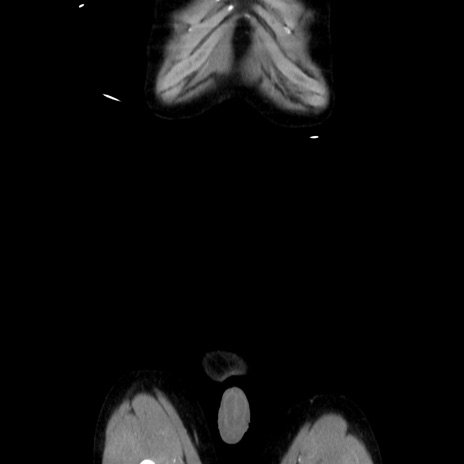

横断像